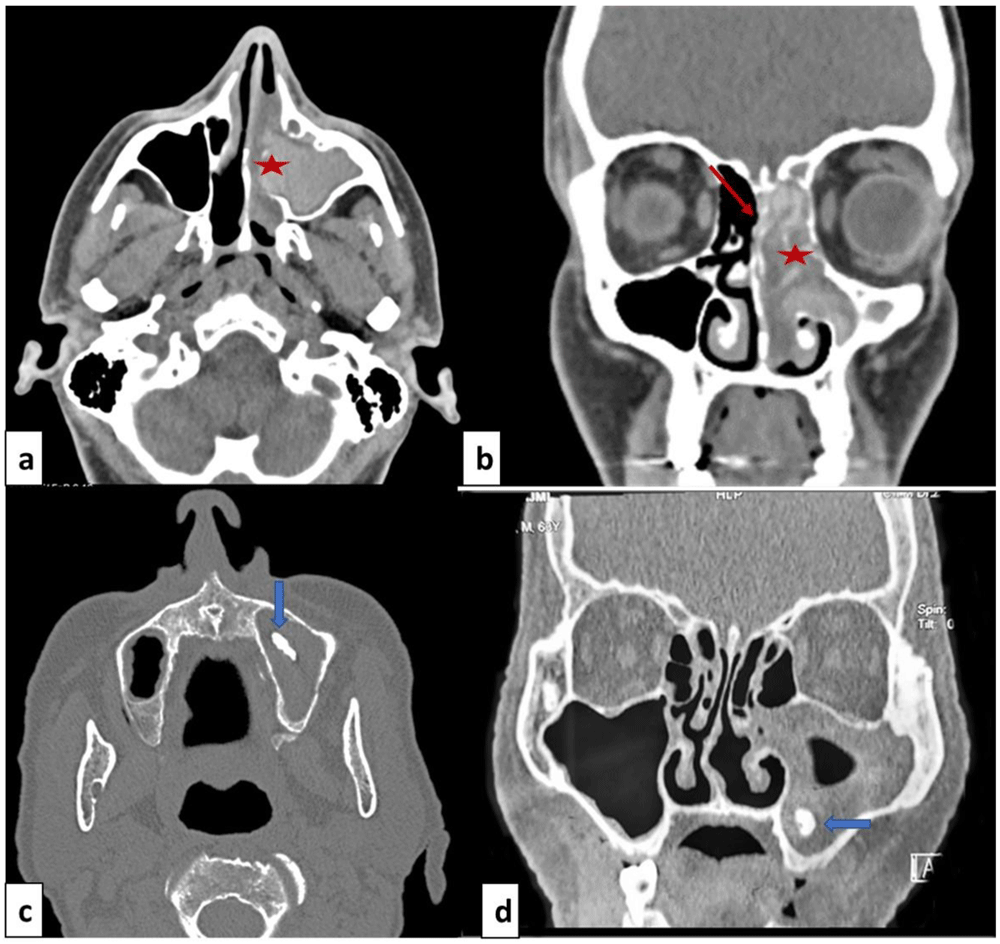

Computed tomodensitometry scan showed opacification of the paranasal sinuses in all patients, unilateral in eight cases (72.7%) and bilateral in three cases (27.3%). The affection consisted of pansinusitis in eight cases (72.7%). The other radiological signs were heterogeneous opacities within the sinus cavity (N=5; 45.5%), local calcifications (N=4; 36.4%) and thinning of the bony walls of the sinuses (N=4; 36.4%) (Figure 1).

Facial mass computed tomodensitometry with axial cut (a, c) and coronal cut (b, d). (a, b): Allergic fungal rhinosinusitis: heterogeneous opacity of the nasal cavity and ethmoido-maxillary cavities (red star) and thinning of the bony walls (red arrow). (b, d): Fungal ball: opacity of the right maxillary sinus with local calcification in maxillary sinus (blue arrow).

The computed tomodensitometry scan images contribute to the diagnosis. In the case of fungal balls, the affection mostly concerns the maxillary sinus. The most reported features were calcifications within the maxillary sinus followed by complete opacification, partial opacification with an irregular surface and bony sclerosis or bone thickening11. These signs remain nonspecific and could be seen in sinusitis of other origins or neoplasms. The MRI is more performant, the fungal ball is hypointense on T1-weighted and T2-weighted images. In the case of allergic FR, scan images typically show bilateral pansinusitis. The opacification of the sinuses is explained by the hyperattenuated mucin. In many cases, as noted for our patients, expansion and thinning of sinus walls were reported. T1-weighted MRI images may show mixed signal intensities. T2-weighted images are mostly hypointense but may show flow voids1.